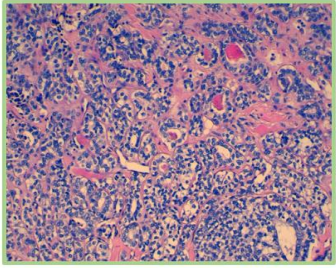

Figure 1: (HE*20): benign tumor proliferation of the parotid gland arranged in tubes, often cystic, suggesting a Warthin tumor

Figure 2: (HE*40): benign tumor proliferation of the parotid gland arranged in tubes, often cystic, suggesting a Warthin's tumor